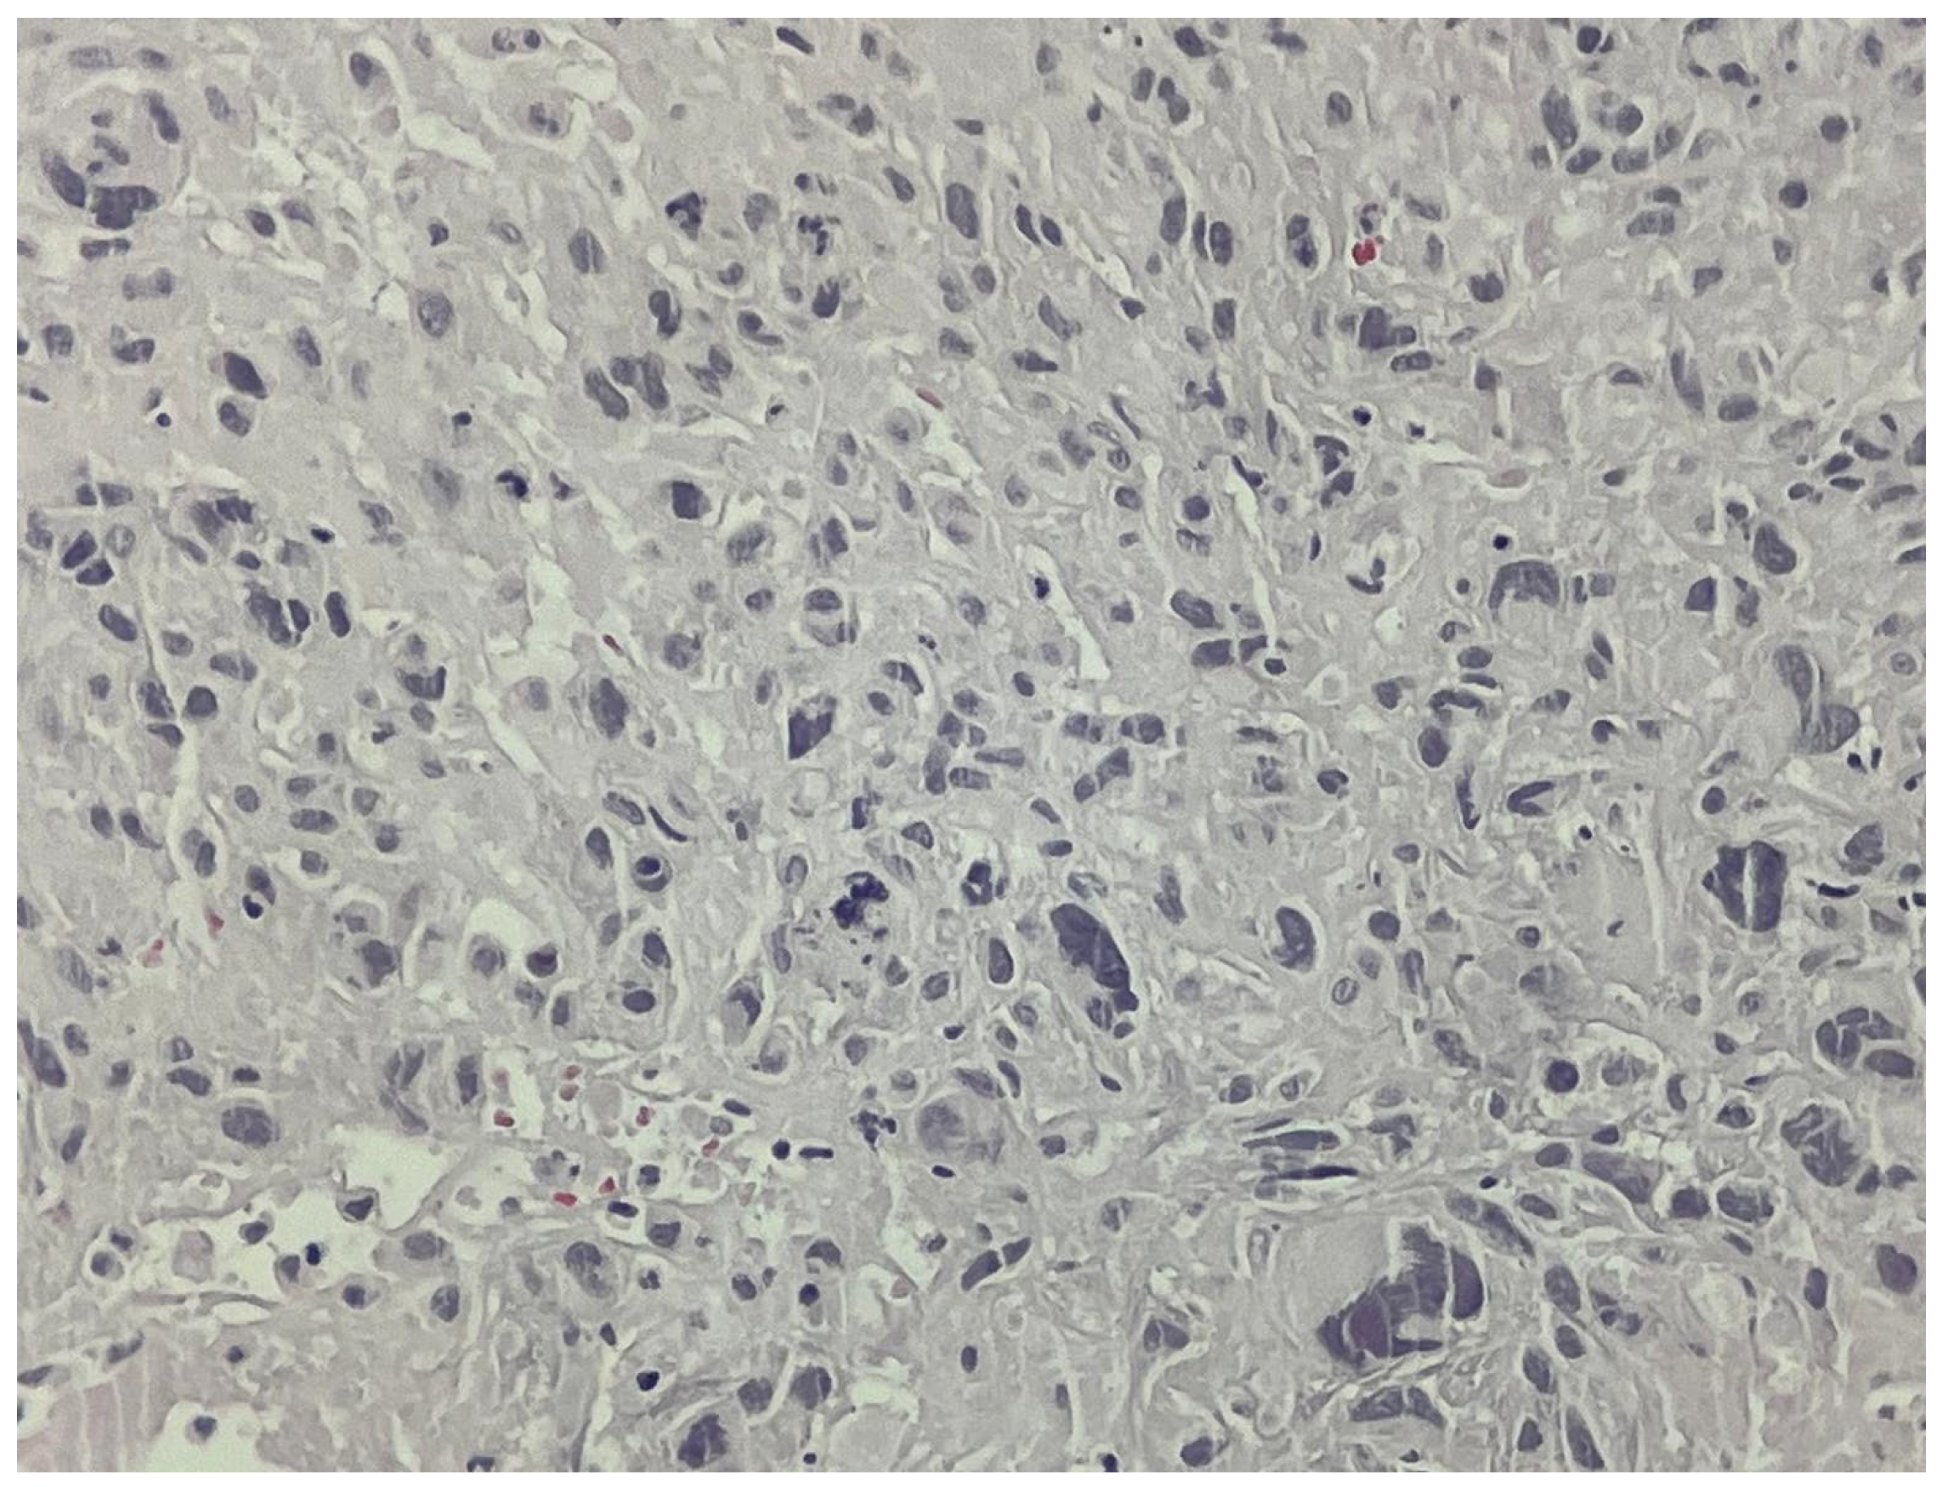

Rare Case of Grade 3 Undifferentiated Pleomorphic Sarcoma in Left Atrium, Mitral Valve, and Papillary Muscle

2. Case Report